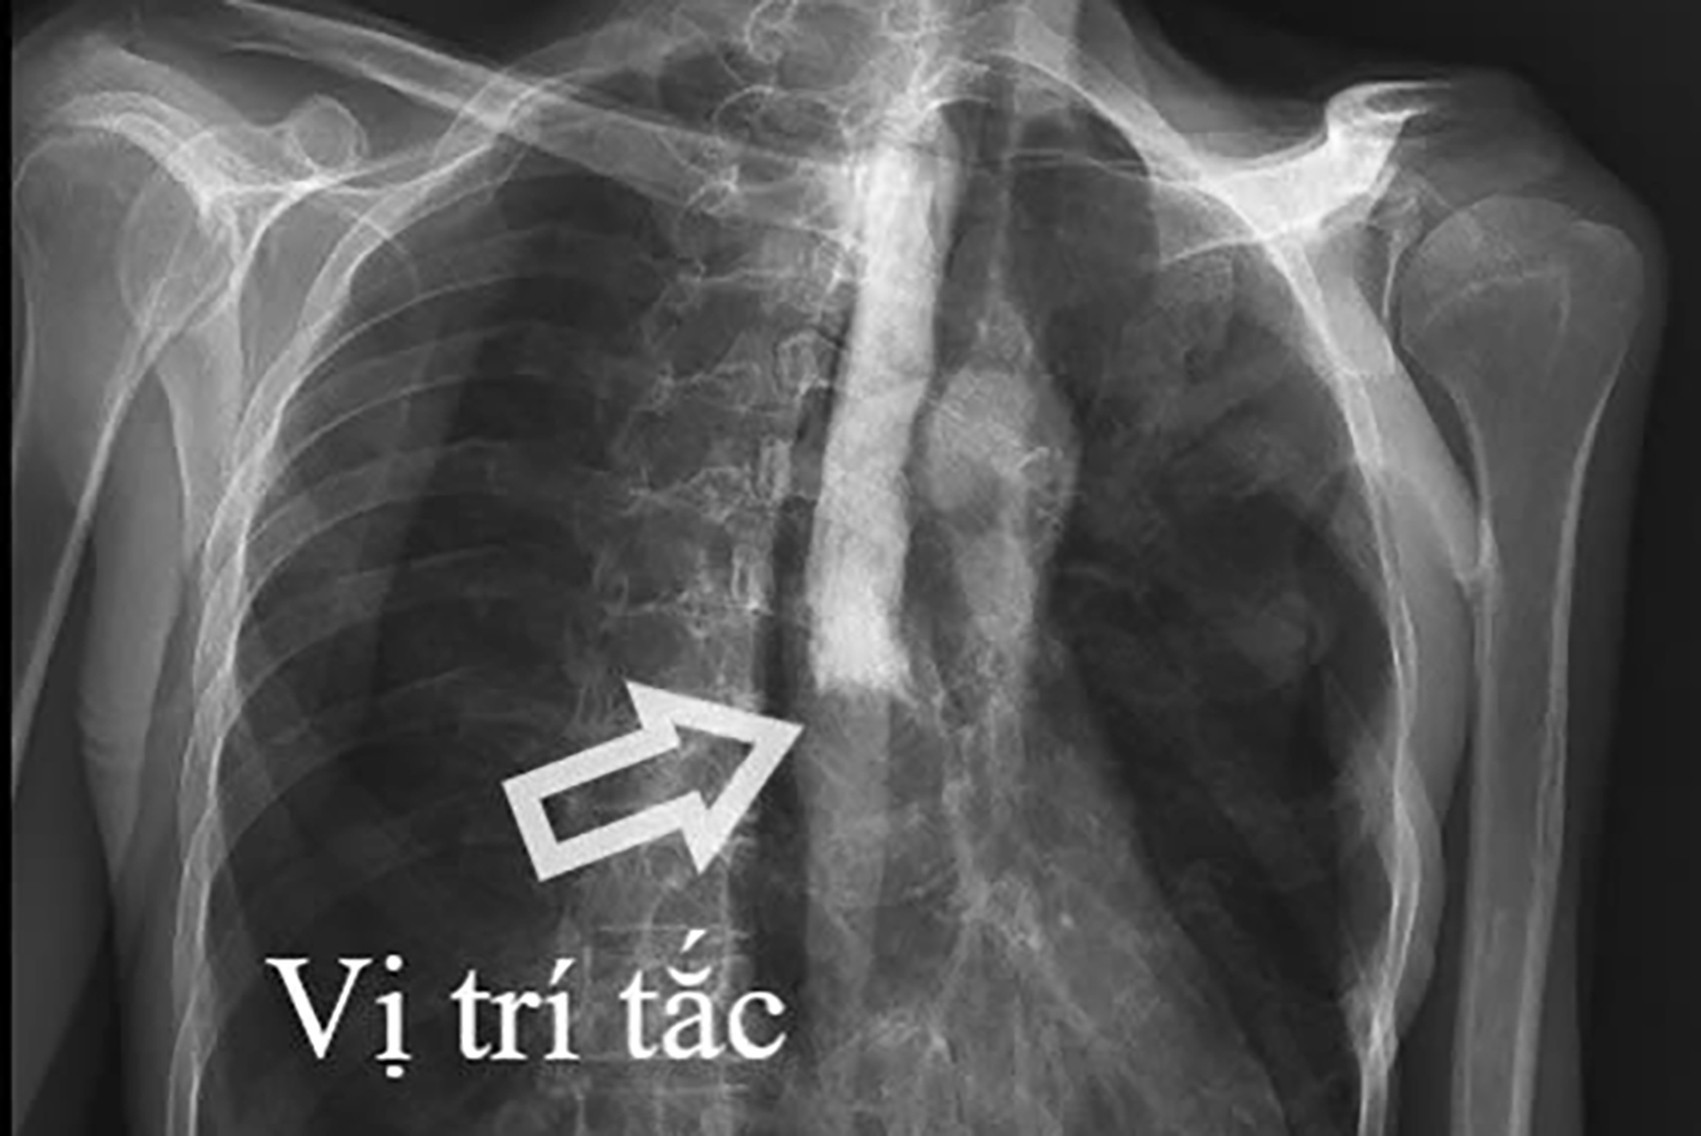

Kết quả cận lâm sàng cho thấy, hình ảnh tắc thực quản hoàn toàn đoạn 1/3 giữa và viêm lan tỏa dạ dày, ruột non, viêm phúc mạc do thủng tạng rỗng.